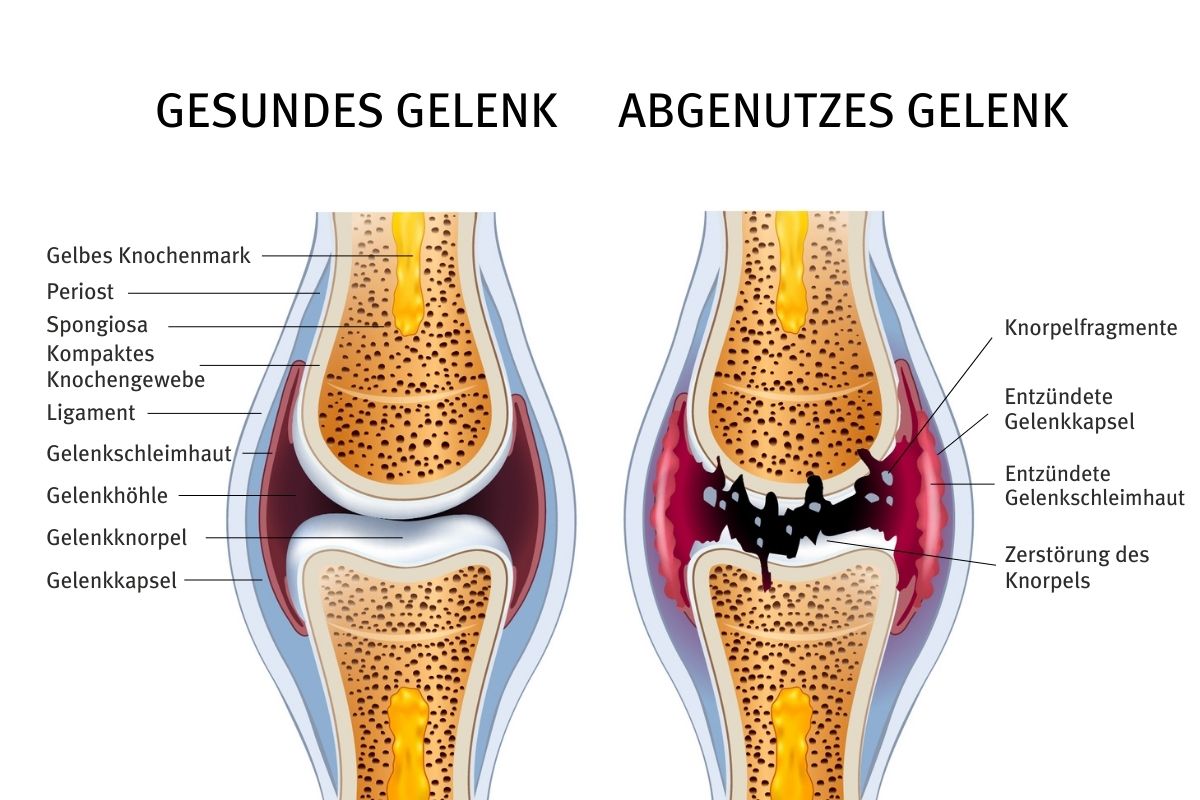

Gelenkbeschwerden können die Folge einer Entzündung sein, die von einem beliebigen Teil eines Gelenks oder der umgebenden Strukturen ausgeht, wie Knorpel, Knochen, Bänder, Sehnen oder Muskeln. In den meisten Fällen entsteht die Entzündung jedoch im Gelenk selbst.

Ein Blick auf die Funktionsweise der Gelenke und den schockierenden Grund, warum sie sich verschlechtern

Das Gelenk ist ein Punkt im Körper, an dem zwei Knochen aufeinandertreffen. Damit sich die Knochen bewegen können, müssen die Gelenke beweglich sein. Je nach dem Umfang oder der Art der Bewegung, die bestimmte Gelenke zulassen, und dem vorherrschenden Anteil des Bindegewebes gibt es drei Arten von Gelenken:

Da Synovialgelenke frei beweglich sind, sind sie anfälliger für Verletzungen und Überlastung als andere Gelenke. Wiederholte Bewegungen und ständige Belastungen führen zu Knorpelabnutzung und Entzündungen in den Gelenken.

Ein gesundes Synovialgelenk besteht aus:

- der Gelenkkapsel – einer faserigen Struktur, die das Gelenk umhüllt

- Bändern – zähes und elastisches Bindegewebe, das das Gelenk umgibt, um ihm Halt zu geben und seine Bewegung zu begrenzen, während es die Knochen miteinander verbindet.

- Knorpel – Gewebe, das die Knochenoberfläche am Gelenk bedeckt und dazu beiträgt, die Reibung während der Bewegung zu verringern

- Synovialmembran– Gewebe, das das Gelenk auskleidet, es in die Gelenkkapsel einschließt und Synovialflüssigkeit um das Gelenk herum absondert

- Synovialflüssigkeit – eine klare und klebrige Flüssigkeit, die das Gelenk schmiert

Obwohl die Gelenke so gebaut sind, dass sie eine Menge aushalten, sind sie nicht unzerstörbar. Und viele Merkmale des modernen Lebensstils tragen zu ihrer raschen Verschlechterung bei. Die Hauptursachen für Gelenkbeschwerden sind in der Regel die Zerstörung von Knorpel, die Lockerung von Bändern oder eine Entzündung der Gelenkschleimhaut.